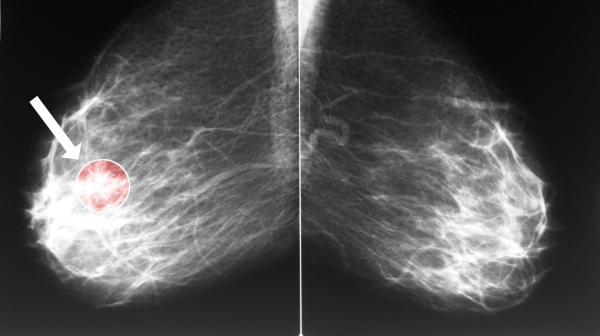

Ученые из Манчестерского университета оценили выживаемость и частоту развития рака молочной железы у носителей мутаций BRCA1 и BRCA2 без онкологического анамнеза, выбравших профилактическую мастэктомию или наблюдение. Результаты исследования опубликованы в Journal of Clinical Oncology.

Анализ показал, что ежегодная частота развития рака молочной железы составила 2,4% в группе наблюдения и 0,15% после профилактической мастэктомии, что соответствует снижению риска появления опухоли на 94%. Во время операции выявили девять скрытых случаев рака, что составило 2% от числа прооперированных.

| Анализировали данные 1205 женщин с патогенными вариантами BRCA1 и BRCA2 без рака молочной железы в анамнезе. Оценивали общую выживаемость, специфическую для рака молочной железы выживаемость и ежегодную заболеваемость. Наблюдение проводили с использованием методов визуализации в соответствии с национальными рекомендациями. |